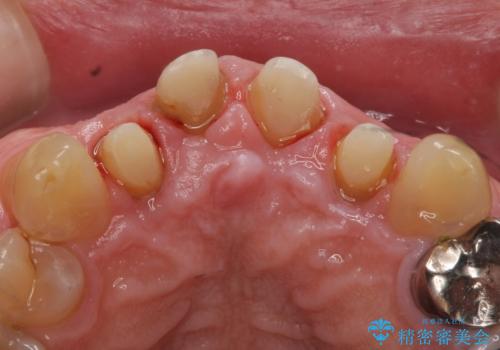

- 前歯の見た目が気になるといらっしゃった方の症例です。

再根管治療後、オールセラミッククラウンによる補綴を行いました。

右上2は歯茎のラインを整えるため歯周外科を行っております。